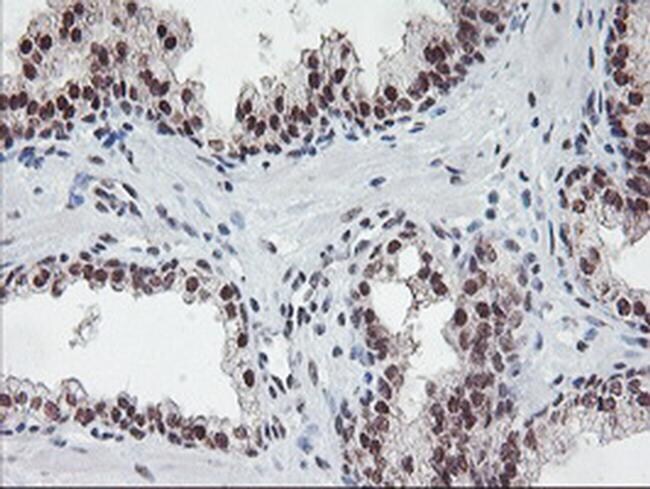

- Immunohistochemical staining of paraffin-embedded Carcinoma of Human prostate tissue using anti-POLR2E mouse monoclonal antibody. (Heat-induced epitope retrieval by 10mM citric buffer, pH6.0, 100°C for 10min, TA502548)

- Submitted by

- Invitrogen Antibodies (provider)

- Main image

- Experimental details

- Immunohistochemical staining of paraffin-embedded Carcinoma of Human bladder tissue using anti-POLR2E mouse monoclonal antibody. (Heat-induced epitope retrieval by 10mM citric buffer, pH6.0, 100°C for 10min, TA502548)